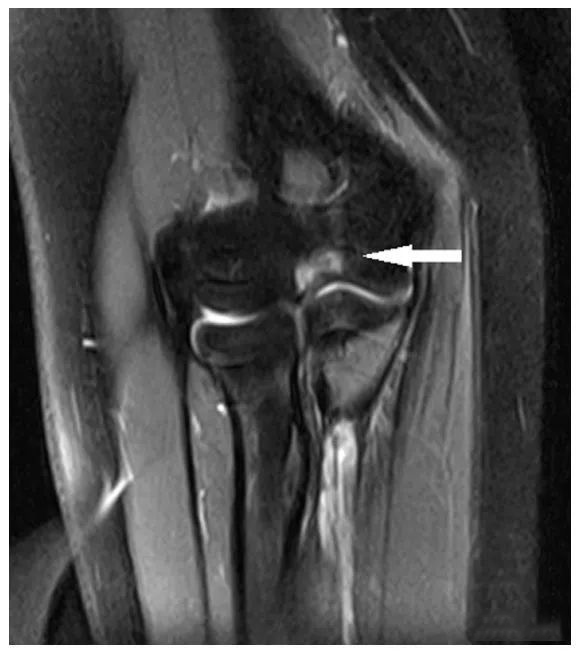

图 1 这位 14 岁的患者表现为慢性肱桡关节半脱位。冠状面 (A) TI 和 (B) PD-FS MRI 图像显示桡骨头相对于肱骨小头的颈向半脱位 (白色空箭头)。桡骨头关节软骨变薄,桡骨头骨髓信号改变 (实白色箭头),符合剥脱性骨软骨炎的特征。

图一